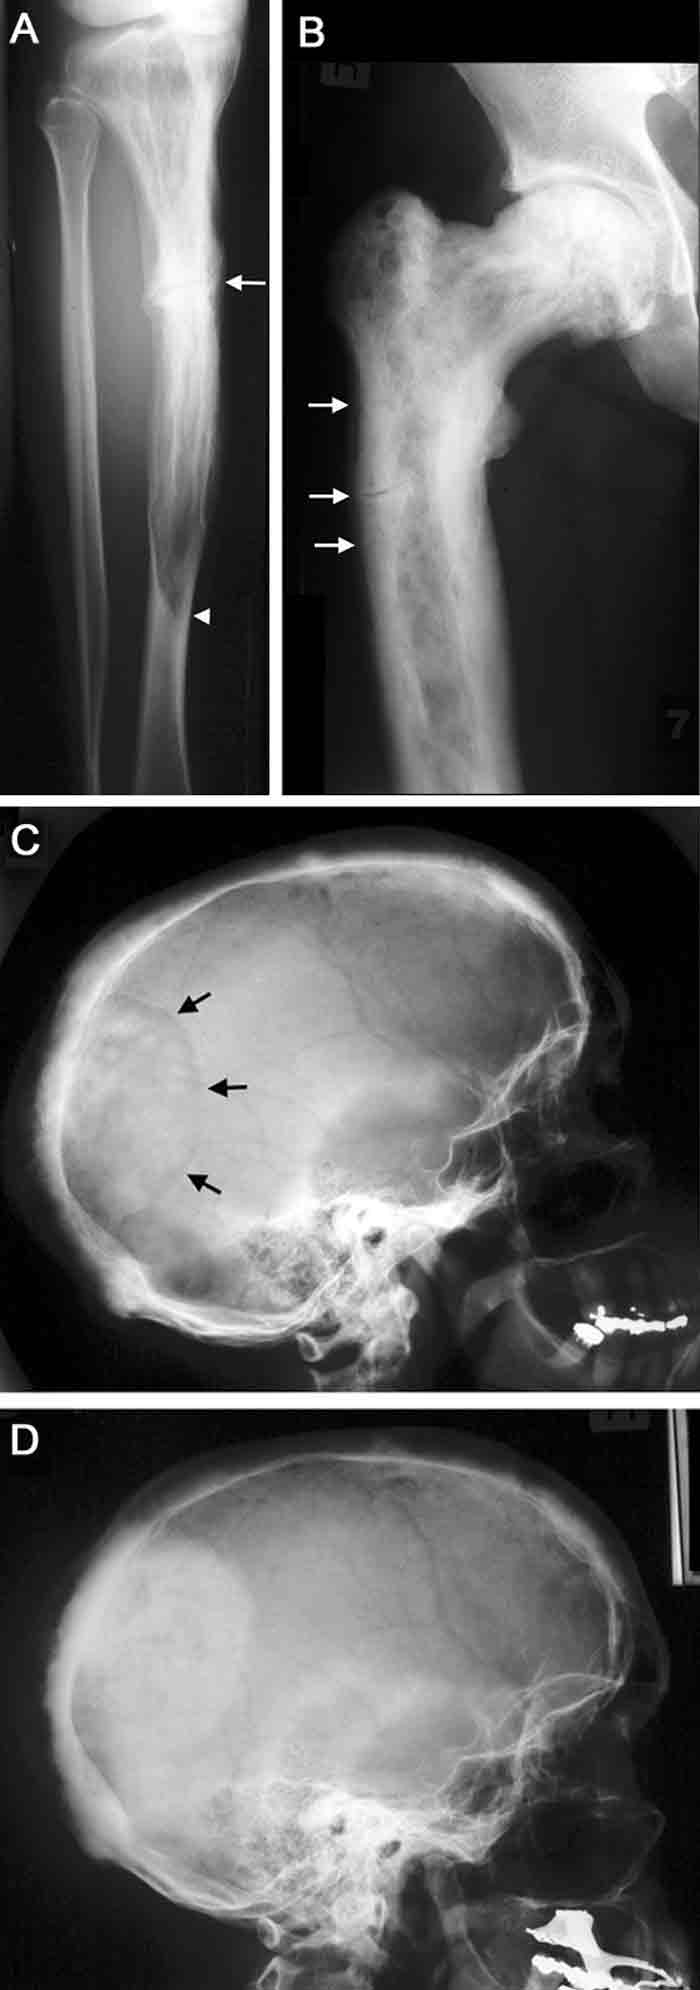

Pagetic bone pain occurs in a minority of patients. Sometimes this has distinct characteristics, being constant (day and night), present at rest and poorly localised, with a dull, boring character. Other patients have more localised pain, worse on weight-bearing and sometimes self-limiting, which may arise from microfractures or localised lytic lesions. Paget’s disease adjacent to a joint can cause secondary arthropathy with the clinical features of osteoarthritis. Deformity, such as bowing of the femur or tibia, may be asymptomatic or associated with mechanical pain in the affected limb or on the contralateral side, arising from secondary gait problems. Cortical fissure fractures arise from abnormal mechanical forces on weakened bone. They may be asymptomatic or painful. They often remain unchanged over time with no response to treatment, but can progress to complete fracture (Box 2).

Paget’s disease is diagnosed primarily by radiological examination. Early in the course of the disease, lytic activity predominates, causing focal osteolytic lesions (osteoporosis circumscripta) or flame-shaped, advancing lytic wedges in the long bones (Box 2A). Subsequently, areas of sclerosis develop, leading to the characteristic appearances of mixed lytic and sclerotic areas, thickened trabeculae, bone expansion, cortical thickening and deformity. The radiological appearances are usually characteristic, but occasionally a differential diagnosis of sclerotic or lytic metastases needs to be considered. An isotope bone scan is recommended in all patients as part of the initial diagnostic assessment to determine the distribution of the disease, in particular the involvement of sites with the potential for complications, such as base of skull, spine and long bones (Box 3). Computed tomography scanning is helpful to assess skull-base involvement (including patients with deafness), spinal stenosis or other neurological complication.